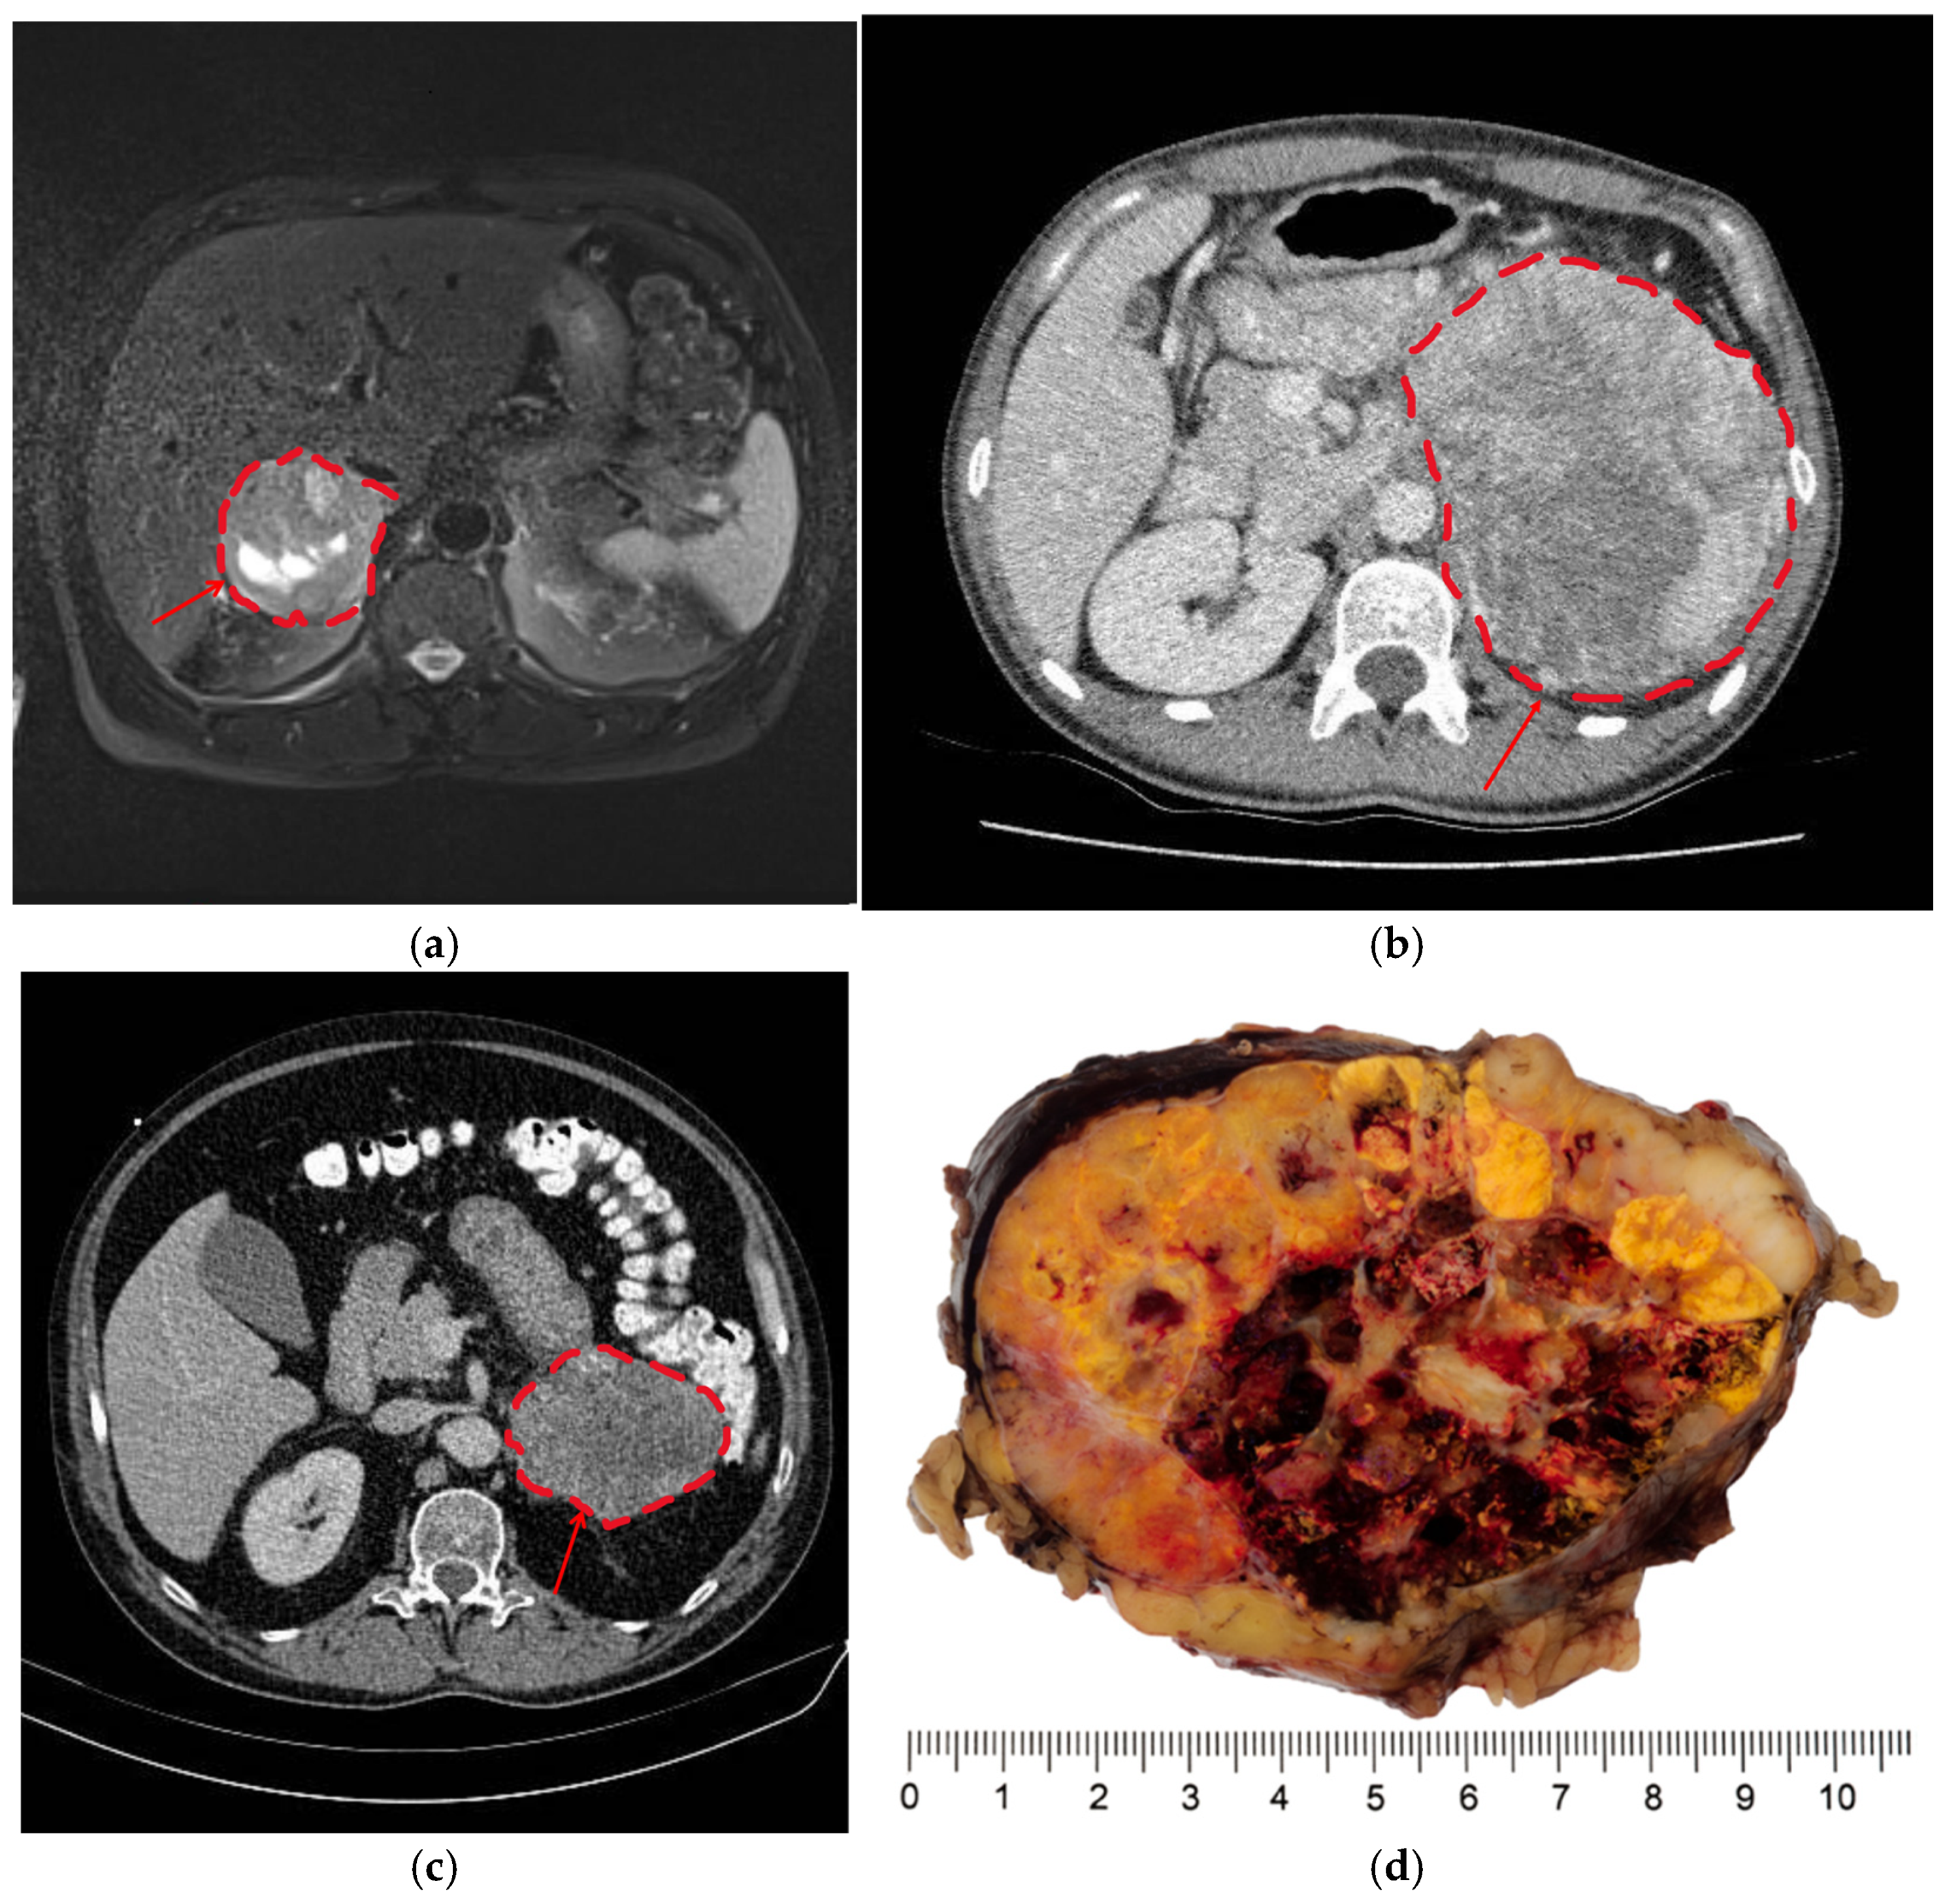

| Areas suspicious of necrosis in cross-sectional imaging 1 | Yes No | 32 (48%) 35 (52%) | 10 (25%) 30 (75%) | 22 (81%) 5 (19%) | <0.001 |

| Areas suspicious of necrosis in histology 1 | Yes No | 27 (40%) 40 (60%) | 1 (2.5%) 39 (97.5%) | 26 (96%) 1 (4%) | <0.001 |